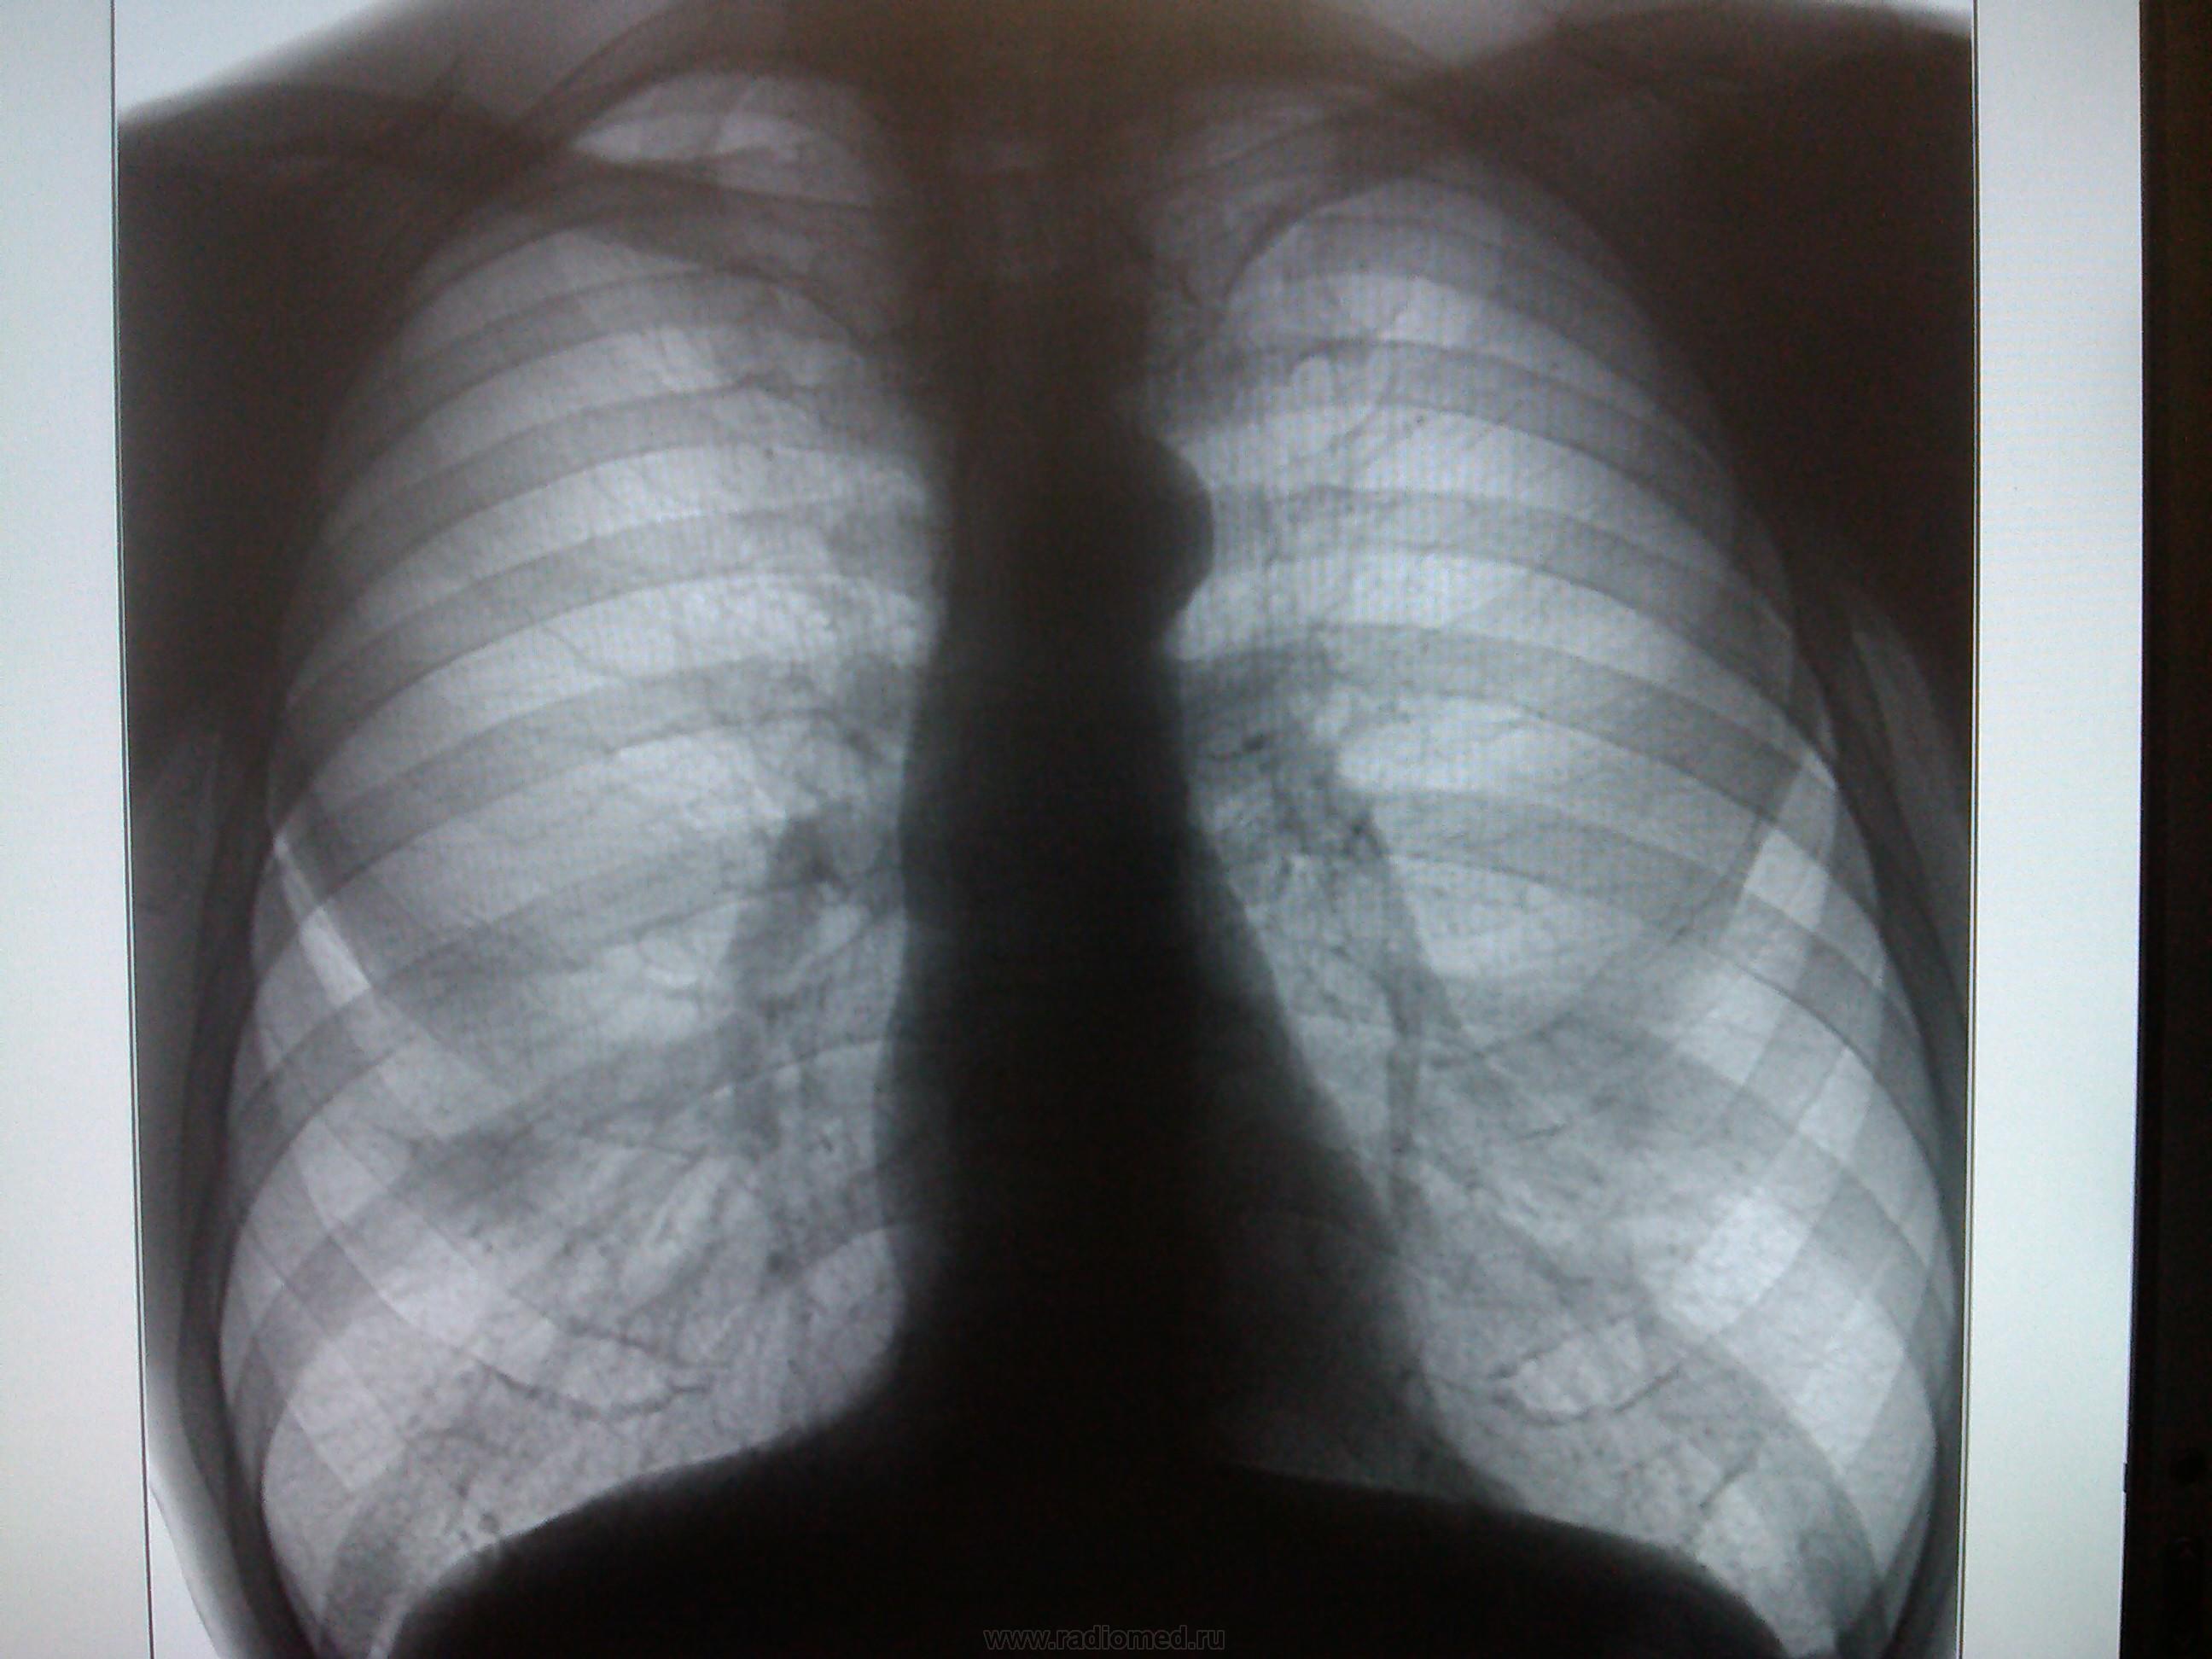

Пациент, 56 лет. Мед. осмотр. Есть ли отрицательная динамика?(или мерещится)

апрель 2013 г.

апрель 2014 г.

Без динамики.

отрицательная динамика чего? по моему норма..

А что за тень на первом боковом снимке за (дорзальнее) тенью корня?

не понравилась эта тень (указана стрел.)

И мне она не понравилась! Сразу обратила внимание. (Но засомневалась, сильно мнительная стала. )

В 2013 году задний синус перекрыт, в 2014 - свободен. Тень, возможно, сосок. Такое подобное с другой стороны. Без скопии не обойтись.

Нужна Р-скопия или хотя бы косой снимок на глубоком вдохе

Так это часть самого корня, на пару с аортой.)

Разницу в синусах можно объяснить различным качеством снимков - цифровой обработкой затушевался синус на первом боковом, но он там есть, ведь хорош на прямом.)

Вывести тень с пересечения 6 и 10 ребер, может и скиалогия